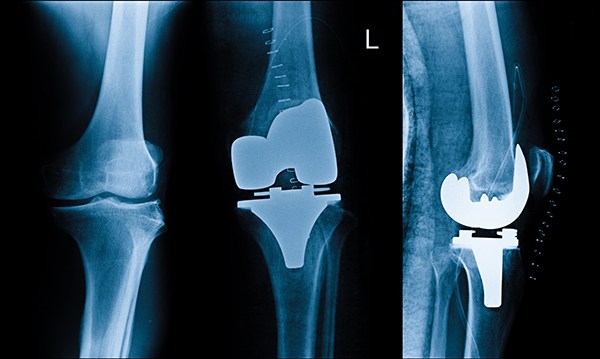

7. خضوع المريض للآشعة بصفة دورية منتظمة لتقييم حالة المفصل ومدى التئام العظام.

يتم الكشف علي المريض وعمل أشعات خاصه لتحديد نوع المفصل المناسب لكل حاله.

يتم زراعة المفصل البديل أما بشكل تقليدي أو عن طريق جراحة طفيفة التوغل، طريقة الزراعة تتعلق بالظروف الفردية والخيارات الخاصة بكل مريض على حدة، في حين أن مخاطر عامة كالعدوى أو اضطراب في شفاء الجرح أو خثرات يمكن أن تحدث، من الممكن أيضا أن تحدث مشاكل خاصة بالمفصل البديل الصناعي، في بعض الحالات يتوجب تبديل بعض المكونات أو المفصل بأكمله في إطار تغيير المفصل البديل.

فى هذه الجراحة بعد تخدير المريض, يتم إزالة الأسطح المتهالكة من عظام الفخذ والقصبة (و الصابونه فى بعض الحالات) وإستبدلها بأجزاء صناعية بحيث يختفي الألم الناتج عن إحتكاك العظام ببعضها ويزداد مدى الحركة فى الركبة وتستغرق الجراحة عادة ما بين 60 – 90 دقيقة على حسب صعوبة الحالة والنوع الذي يعتمد علي سعر الركبة الصناعي ومن مزايا هذه الجراحة أن أي أعوجاج (تقوس) بالساق يتم إصلاحه من خلال الجراحة نفسها ويستطيع المريض المشي على رجله فى اليوم التالي للجراحة مباشرة بمساعدة عكازات. ويمكن إجراء هذه الجراحة من خلال جرح صغير كما أن هناك تقنيات حديثة مثل المفصل ثلاثي الأبعاد تستخدم فى بعض الحالات واستخدام الروبوت فى إجراء الجراحة.

ويتكون مفصل الركبة الصناعي من جزء معدني يغطي سطح عظمة الفخذ وآخر يغطي القصبة وبينهما مادة بلاستيكية بيضاء ذات قوة عالية لمنع الأحتكاك بينهم وفى حالات قليلة قد يتم تركيب جزء بلاستيكي يغطي سطح عظمة الصابونة (الردفة) ويتم تثبيت هذه الأجزاء فى العظام عادة بواسطة مادة تسمى الأسمنت العظمي وهناك انواع من مفاصل الركبة الصناعية يتم تركيبها بدون أسمنت طبي ولكن إستخدامها غير شائع نظرا لإرتفاع تكلفنها وعدم ثبوت تميزها عن المفاصل الأسمنتيه.

تعتبر جراحة مفصل الركبة الصناعية من الجراحات المكلفة بعض الشيء وذلك نظرا لتضمنها ثمن المفصل الصناعي نفسه والمستلزمات الخاصة بتركيبه وبصفة عامة يقوم الطبيب بتقدير تكلفة عميلة تغيير مفصل الركبة في الحبيب بعد فحص المريض والإطلاع على أشعاته لتحديد نوع المفصل المناسب لحالته تكلفة عملية الركبة الصناعية. تكلفة عملية الركبة الصناعية